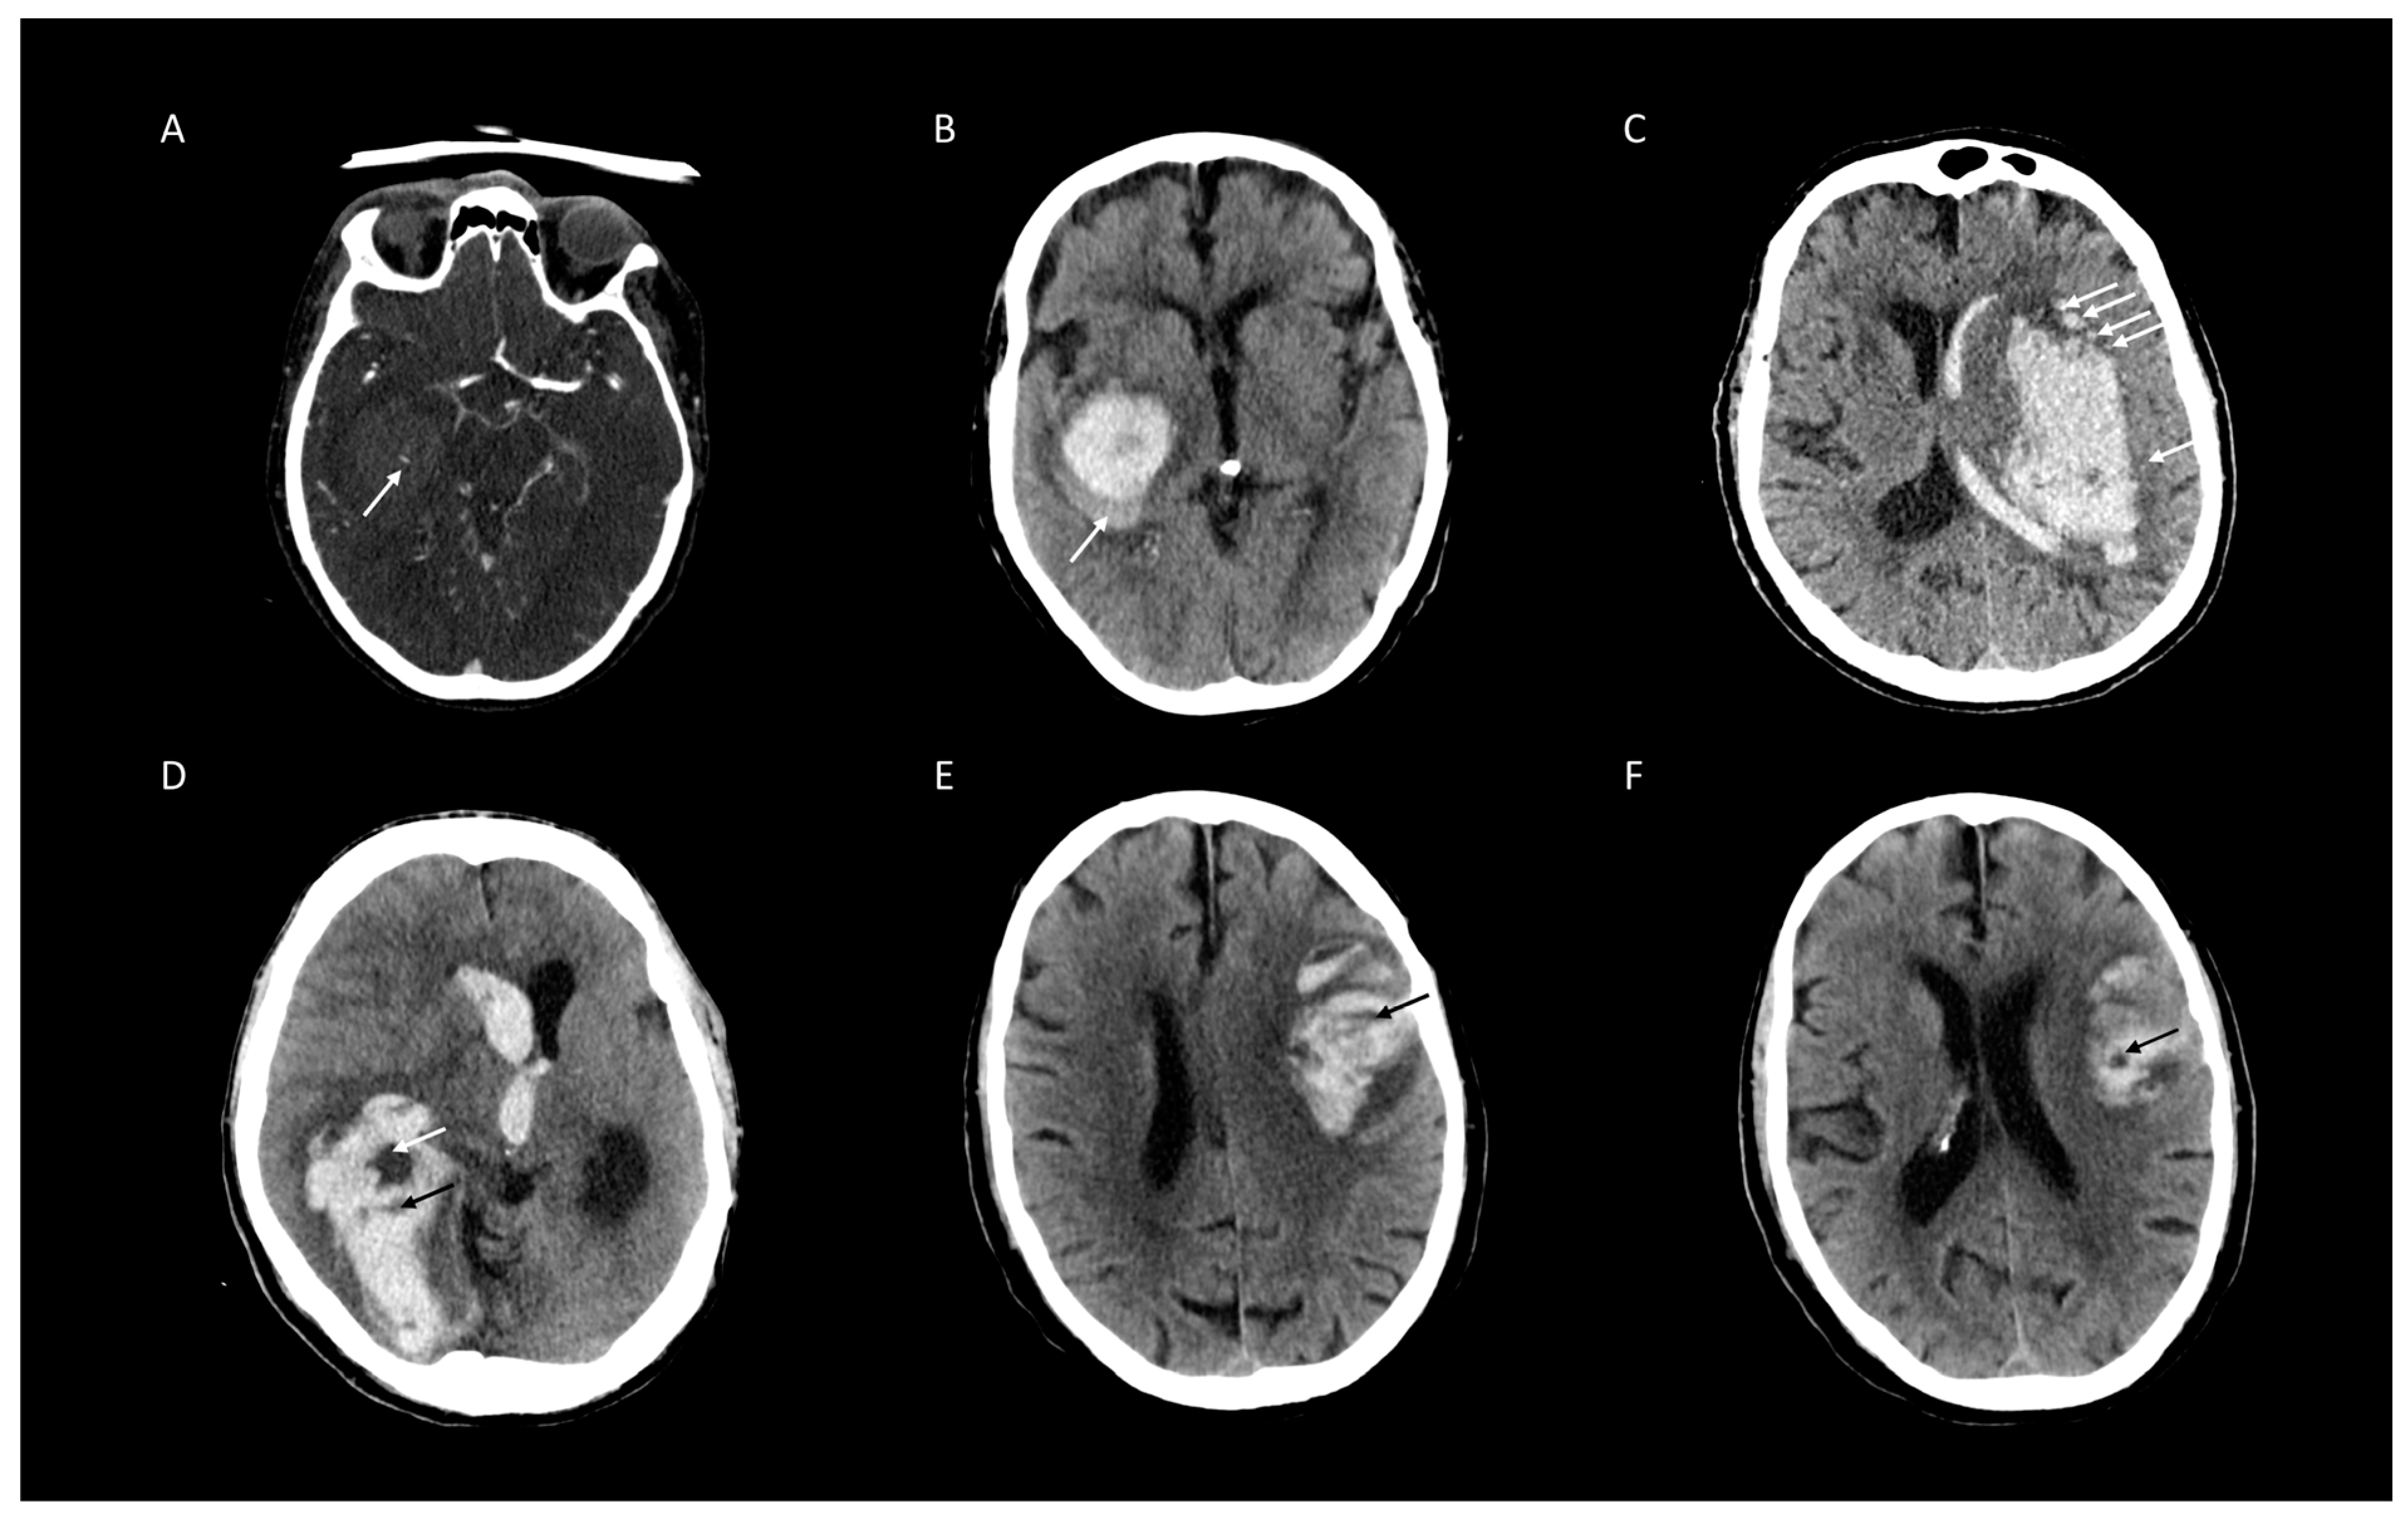

2.3. Image Analysis